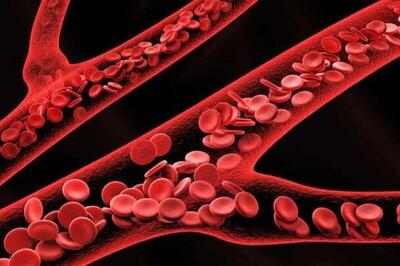

شناسایی یک گروه خونی جدید پس از 50 سال

پس از گذشت حدود پنج دهه از آزمایش خونی که فاقد یک مولکول سطحی بود، در نهایت یک گروه خونی